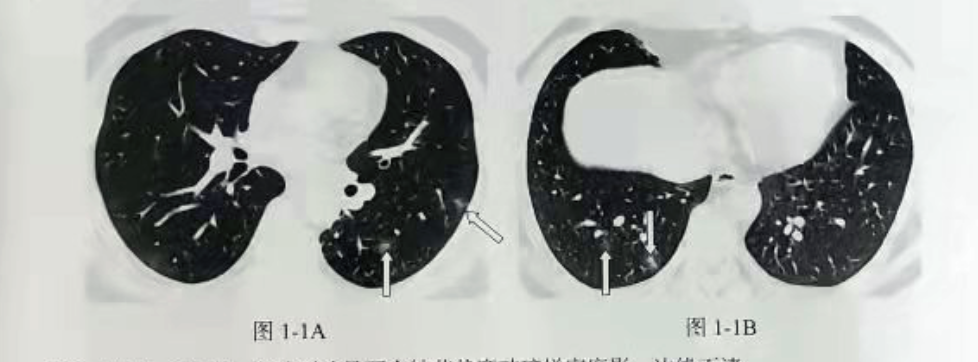

新型冠状病毒肺炎(COVID-19)早期可表现磨玻璃样密度影,边界不清,以胸膜下或支气管血管束周围分布为主;病理提示为肺泡腔内和肺泡间隔的炎性渗出。影像表现主要分为结节状、斑片状或片状磨玻璃样密度影,病灶可相对局限或弥漫,随着病情进一步发展,局部合并实变影。

参考书籍《COVID-19 影像与临床诊断》